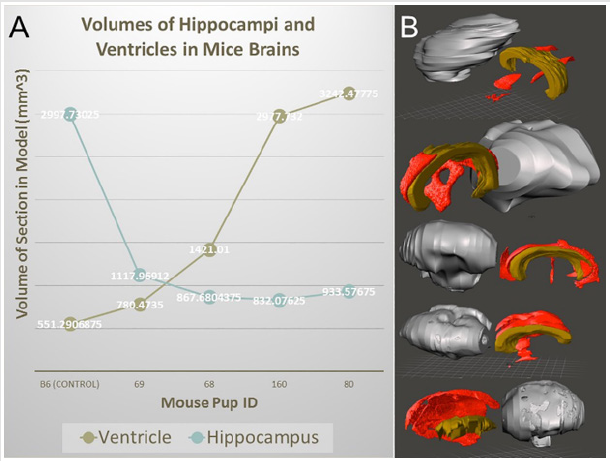

There are countless other tools that can be used to edit the model if necessary, however these three are integral in optimizing the model. It was also observed that image stacks from ECM had dimensions on the scale of five to ten meters. This is an example of another incompatibility between preclinical imaging modalities and human modalities and can be fixed using the resize tool available in the Meshmixer software. It is a simple tool to manually resize the model by dragging the cursor. Ultimately, reducing the file size of the model gives it much more versatility, reducing time taken to view and edit the file, increasing compatibility with weaker computers, and increasing ease of file sharing with other computers. This final file can also be saved and used for digital phenotyping, as it is an accurate representation of the genetic model in 3D form. It can be sliced in any direction using the place cut tool to view internal cavities and deformities making it a very versatile model. In addition to printing physical models, the segmentation and rendering models can provide volumetric information. Figure 6 shows 3D rendering and segmentation outcomes from various mutant mouse brains from micro-MRI source data.

Figure 6: 3D surface rendering and segmentation for mouse brains from micro-MRI source data files. (A) volumetric analysis of ventricles and hippocampi of various mutant mouse brains. (B) 3D rendering and segmentation of the cerebrum (gray), ventricles (red), and hippocampus (brown) from various mutant mice.